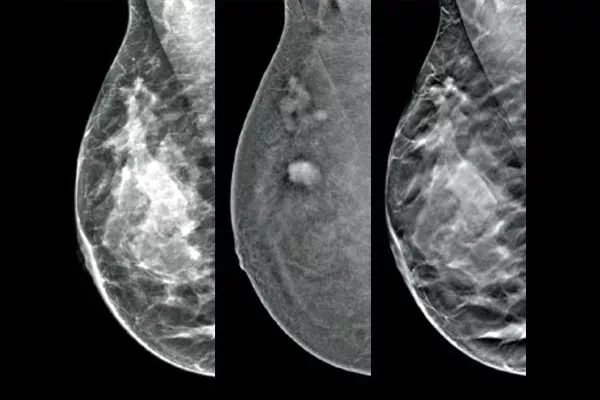

Die Affirm® Lösung für die kontrastverstärkte Biopsie ermöglicht das Targeting und die Entnahme von Brustgewebe bei Läsionen, die während der Kontrastmittel-Mammographie (CEM) identifiziert wurden. Die zur Maximierung der Workflow-Effizienz bei gleichzeitiger Verbesserung des Patientenkomforts konzipierte Lösung für die kontrastverstärkte Biopsie vereinfacht die Brustbiopsie, selbst bei herausfordernden Verdachtsmomenten.

Targeting und Biopsie von Läsionen, die mit der kontrastverstärkten 2D-Mammografie erkannt wurden, anhand eines stereotaktischen Verfahrens mit vergleichbarer diagnostischer Leistung wie die Brust-MRT.1,2 Vergleich von Bildern nach Markierung in derselben Modalität in der die diagnostische Erstuntersuchung mit Kontrastmittel durchgeführt wurde.

Die Affirm Software für die kontrastverstärkte Biopsie ermöglicht die Durchführung einer Biopsie an Läsionen, die bei der I-View™ kontrastverstärkten 2D-Mammografie identifiziert wurden. Durch die Fähigkeit, kontrastverstärkte 2D- und Tomosynthese-Aufnahmen unter einer Kompression zu erstellen, ermöglicht das4 Affirm Steuerungssystem für aufrechte Brustbiopsien einen zügigen Übergang von der Früherkennung zur Biopsie. Dabei wird dieselbe bewährte Bildgebungskette5 wie beim Mammografiesystem genutzt, um die 3D™ Visualisierung verdächtiger Läsionen zu verbessern.

Eine effiziente und kosteneffektive Alternative zur MRT

Die funktionelle Bildgebung unter Verwendung von CEM bietet gegenüber der Brust MRT dank ähnlicher Sensitivität, höherer Spezifität und eines höheren positiven Vorhersagewerts Vorteile.7,8 Zusätzlich dazu stellt die CEM im Vergleich zur MRT aufgrund der kürzeren Verfahrensdauer7,10 eine kosteneffektive Alternative für die diagnostische Bildgebung dar.9